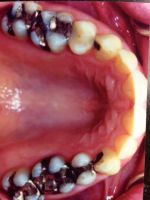

Onlays and Inlays

Before

After